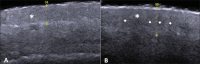

The present essay is aimed at getting the radiologist familiar with the basic histological skin structure, allowing for a better correlation with sonographic findings. A high-frequency (22 MHz) ultrasonography apparatus was utilized in the present study. The histological analysis was performed after the skin specimens fixation with formalin, inclusion in paraffin blocks and subsequent staining with hematoxylin-eosin. The authors present a literature review showing the relationship between sonographic and histological findings in normal cutaneous tissue, and discuss the technique for a better performance of the sonographic scan. High-frequency ultrasonography is an excellent tool for the diagnosis of different skin conditions. However, as this method is operator-dependent, it is crucial to understand the normal skin structure as well as the correlation between histological and sonographic findings.